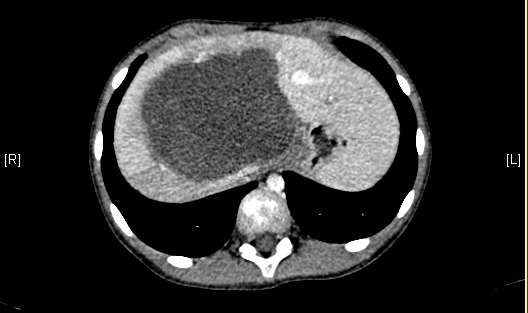

术前CT检查:

静脉期

腹部超声示:肝内包块。腹部CT:肝脏占位,血管瘤?上腹部增强CT:肝左内叶-右前叶交界区、尾叶囊实性团块影,考虑肿瘤(胆管囊腺瘤?间叶性错构瘤?)